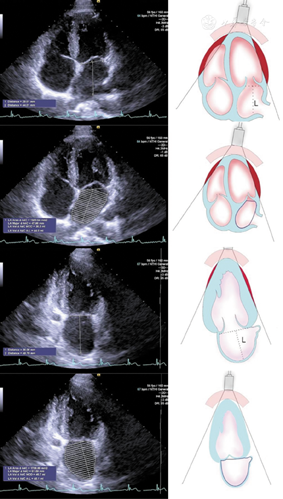

图19

标准心尖四腔切面和两腔切面引导采用Simpson双平面法进行左心室舒张末期和收缩末期容量测量方法,采用同步心电图确定准确舒张末期和收缩末期时相